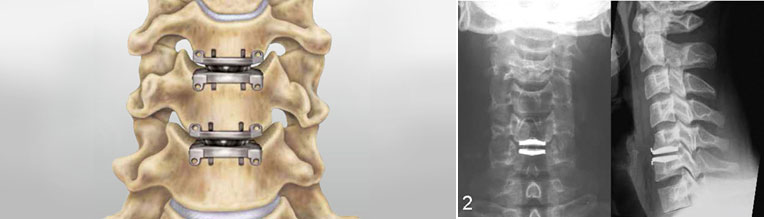

• Disc replacement: Replacing the injured disc with an artificial one.

• Spinal fusion: Joining 2 vertebra with bone graft.